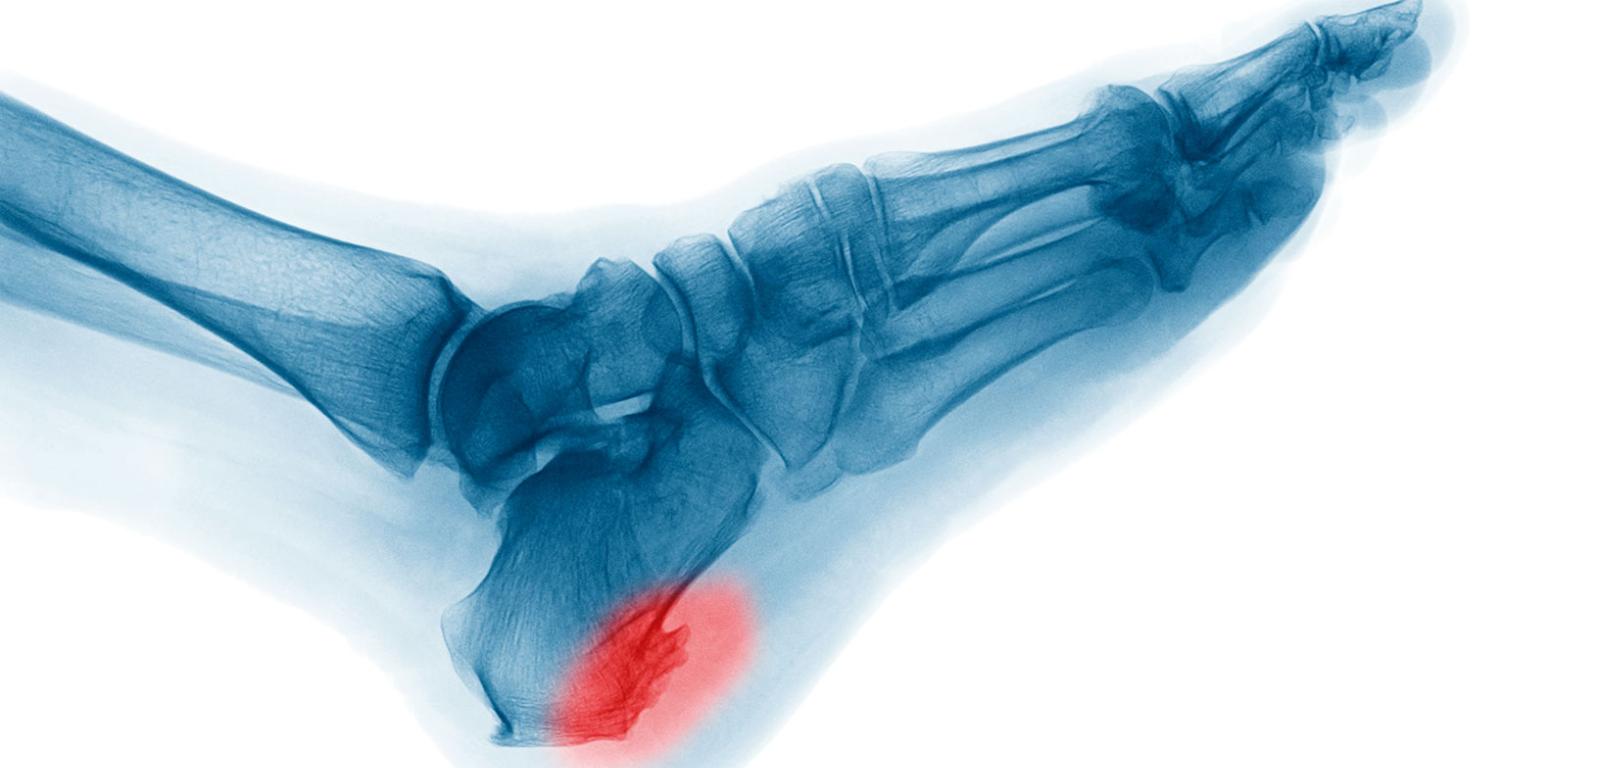

Nadmierne odkładanie się wapnia powoduje powstanie ostrogi piętowej, która uciskając nerwy, sprawia przewlekły ból. Nadmierne odkładanie się wapnia powoduje powstanie ostrogi piętowej, która uciskając nerwy, sprawia przewlekły ból. Suttha Burawonk / Shutterstock